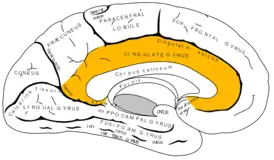

![]() Медиальная поверхность левого полушария. Поясная извилина и поясная борозда выделены жёлтым цветом. | |